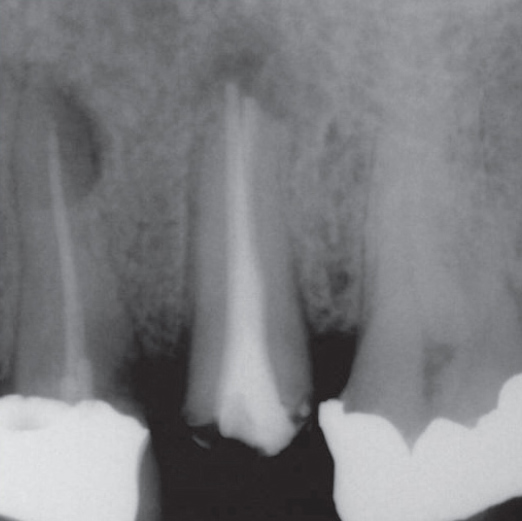

After

After Root Canal treatment